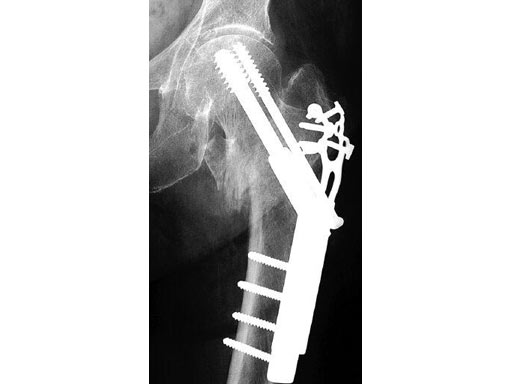

The Locking Trochanter Stabilization Plate is intended for the treatment of unstable pertrochanteric fractures in combination with the Dynamic Hip Screw (DHS), especially for 4-part fractures with greater trochanter.

Using the plate limits the possibility of varus deformation of the proximal fragment by cutting out the screws and medialization of the distal femoral fragment, without impairing the function and dynamization capacity of the DHS. The Locking Trochanter Stabilization Plate limits diaphyseal medialization by fastening onto the greater trochanter relief. The additional proximal internal fixaton can be achieved by using 3.5 mm locking head screws.

79-year-old woman.